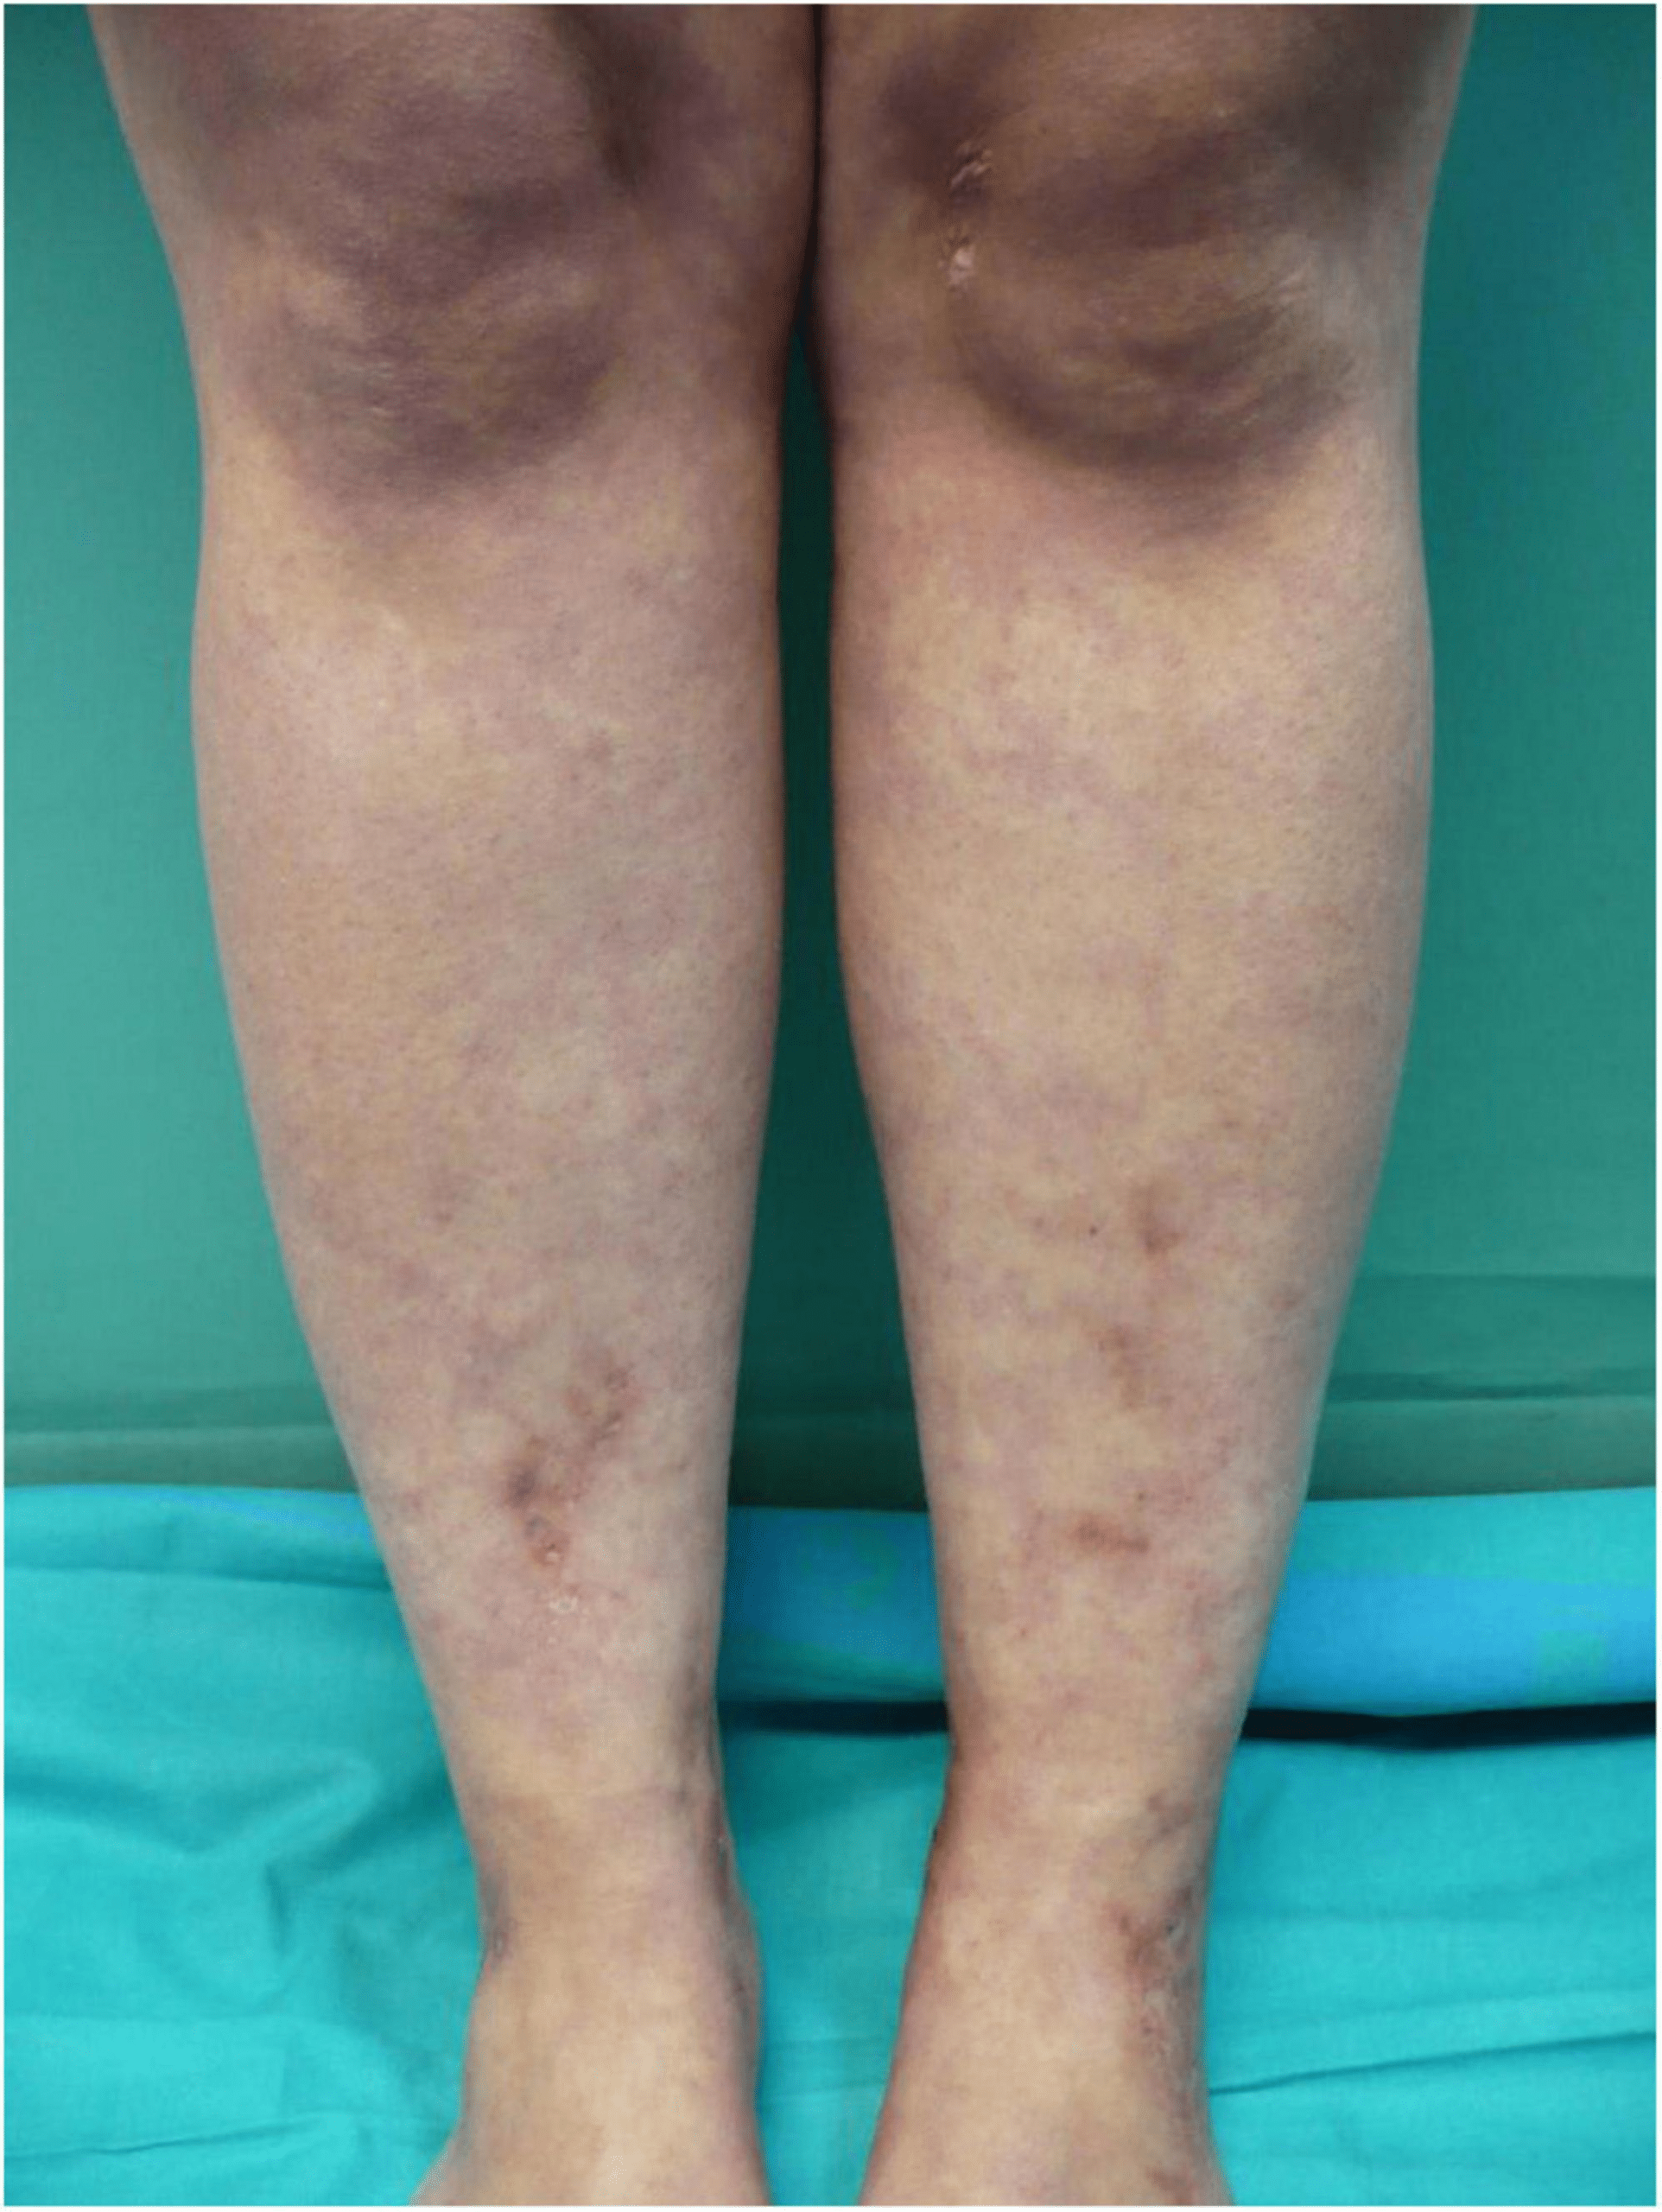

Varicose veins develop when vein valves weaken or fail, allowing blood to pool in the legs instead of flowing efficiently back to the heart. This leads to bulging veins, swelling, aching, heaviness, and sometimes skin changes or ulcers in advanced cases. Risk factors include age, prolonged standing or sitting, pregnancy, obesity, and family history. Poor circulation exacerbates symptoms, causing fatigue in the legs and reduced quality of life. While lifestyle changes like movement, elevation, and compression stockings help manage it, no single nutrient “opens” veins instantly or reverses structural damage in one dose.

The images in these posts often exaggerate changes—real vein improvement takes time, and dramatic overnight fixes from a vitamin alone lack scientific backing. Many such claims promote supplements with overstated benefits, sometimes bordering on misleading marketing.